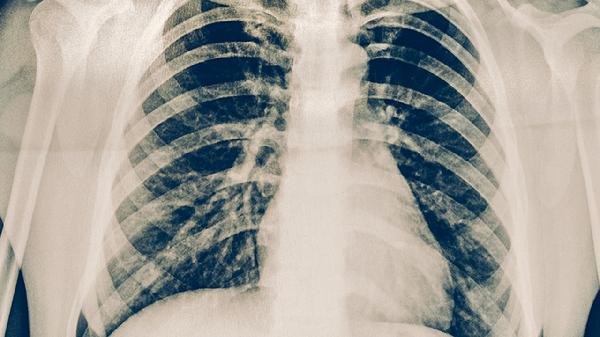

胸部X線能顯示肺結(jié)核特征性病變,如上肺野浸潤(rùn)影、空洞形成等典型表現(xiàn)。該檢查對(duì)肺外結(jié)核診斷價(jià)值有限,且需與肺炎、肺癌等疾病鑒別?;顒?dòng)性肺結(jié)核患者常見多形態(tài)病灶共存,陳舊性結(jié)核則以纖維鈣化灶為主。建議結(jié)合臨床癥狀和其他檢查綜合判斷。